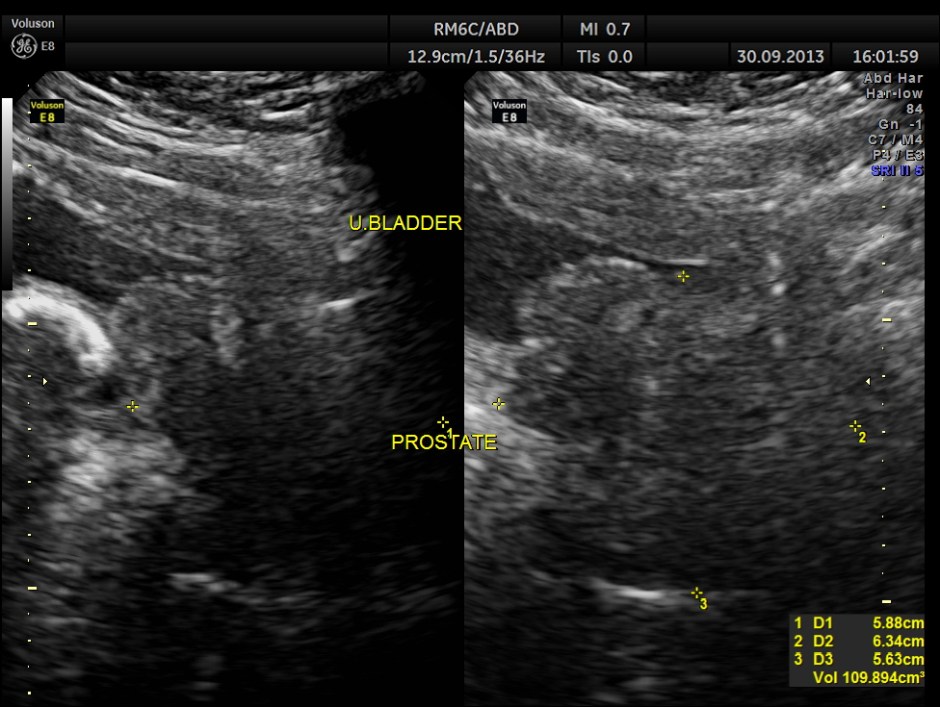

urinary bladder showed a large calculus and prominent swelling of the median lobe of the prostate.

enlarged prostate and median lobe hypertrophy

the median lobe hypertrophy in 2 D

The diagnosis given was Large calculus in the urinary bladder , Severe prostatic enlargement with prominent median lobe hypertrophy , causing Right sided obstructive uropathy.

The diagnosis was made with the 2D images , but the 3 D images were very helpful in explaining to the patient.